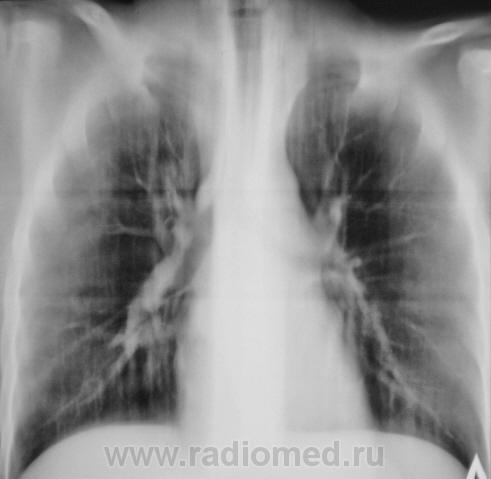

"Зацепился глаз" за "подчеркнутость" контура бронха справа.

Добрый вечер, Валентин Львович! Бронхоскопия это хорошо, но растолкуйте, на основании чего - тени слепленой из пересечения пары артерий и вены? или что?

Я Вас прекрасно понимаю, но при расшифровке флюорограмм, именно стенка бронха показалась плотноватой, вот и взяли, и распилили, потом долго глядели, и решили...

Плевро-медиастинальная спайка справа, больше ничего не высмотрел.